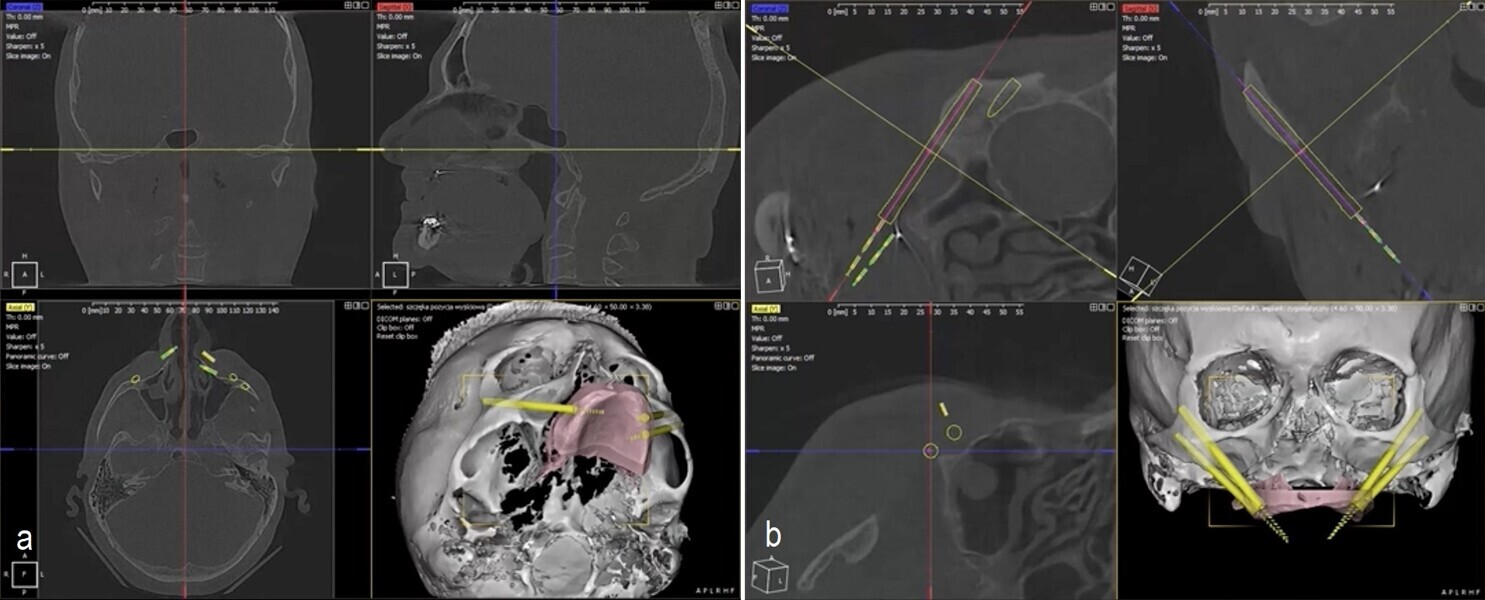

Planning incorporates data from CBCT scans and intra-oral scans to develop a detailed digital model of the patient’s anatomy, supporting accurate implant and maxillary positioning. A particularly important step involves an additional CBCT scan with radiopaque markers to align soft tissue data with the CBCT scan. This integration allows for the creation of customised surgical guides that reflect the patient’s true anatomical structure, ensuring safer and more precise execution.

During surgery, I use two 3D-printed surgical guides: one affixed before the osteotomy to guide implant and anchor pin positioning, and the second used after repositioning the maxilla to confirm implant alignment and skeletal placement. This workflow enhances reproducibility and reduces human error, the only variable being the quality of diagnostic data.

I recently applied this technique in the treatment of a 69-year-old patient with longstanding edentulism and advanced maxillary bone loss. The procedure, planned entirely with DDS-Pro, allowed for accurate implant placement and maxillary repositioning (Figs. 1–4). Carried out under general anaesthesia, the surgery took approximately 2 hours and was completed without complication (Figs. 5 & 6). The surgical guides functioned exactly as expected, leading to a stress-free operation.